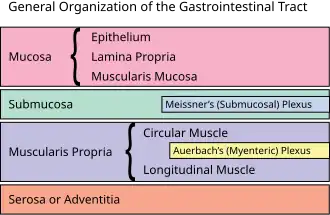

The myenteric plexus (or Auerbach's plexus) provides motor innervation to both layers of the muscular layer of the gut, having both parasympathetic and sympathetic input (although present ganglion cell bodies belong to parasympathetic innervation, fibers from sympathetic innervation also reach the plexus), whereas the submucous plexus provides secretomotor innervation to the mucosa nearest the lumen of the gut.

A part of the enteric nervous system, the myenteric plexus exists between the longitudinal and circular layers of muscularis externa in the gastrointestinal tract. It is found in the muscles of the esophagus, stomach, and intestine.